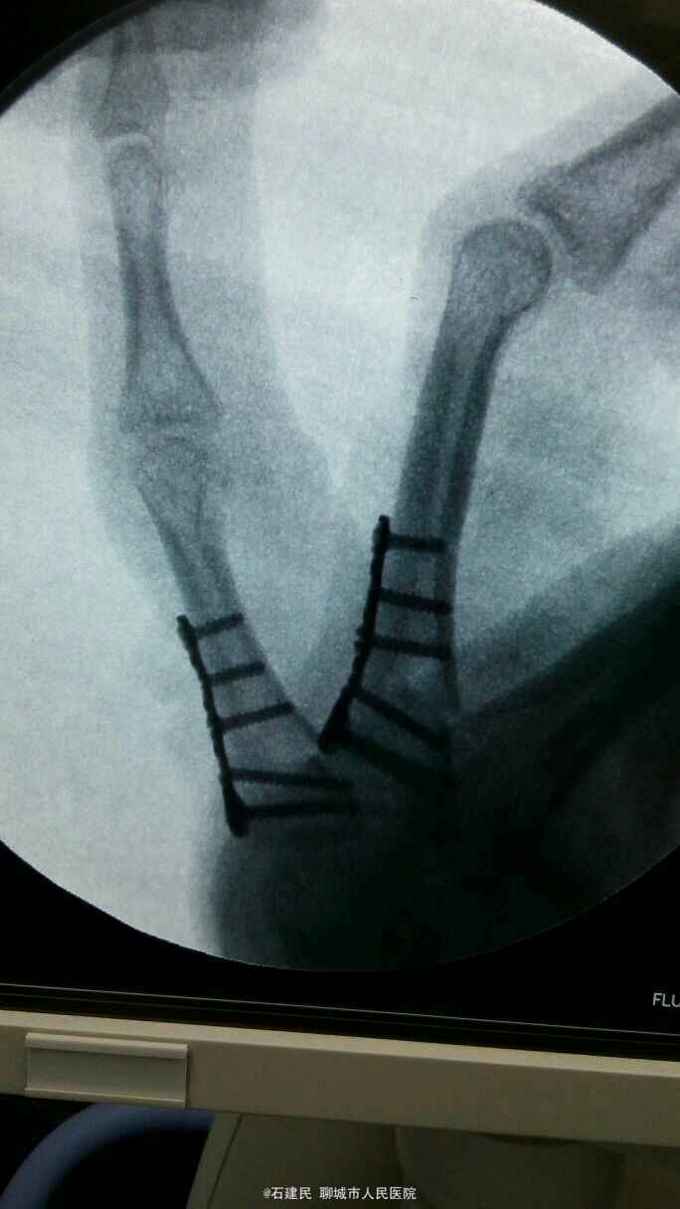

患者外伤致手部肿痛畸形,活动不能来我院就诊,行X线示环小指指骨骨折,收住院治疗。

查体可见神志清,精神正常,手背明显肿胀,畸形,环小指活动不能。

环小指指骨骨折,给予行切开复位内固定术,术中见环小指指骨近端骨折较短,给予行T型刚板固定。

患者骨折靠近掌骨基地部,单纯闭合复位很难固定,术后石膏保护3周,3周后去除石膏外固定主动活动锻炼。